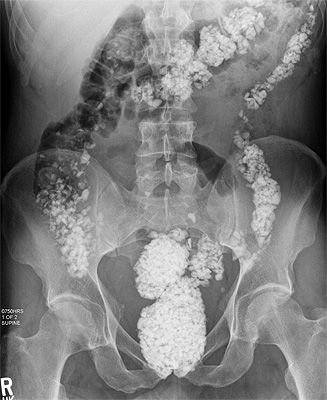

Abdominal x-ray films showed small radio-opaque foreign bodies scattered throughout the entire colon.

The patient admitted to having ingested small pebbles and gravel over the past 9 months, with the belief that "God might turn it to bread in his belly.”